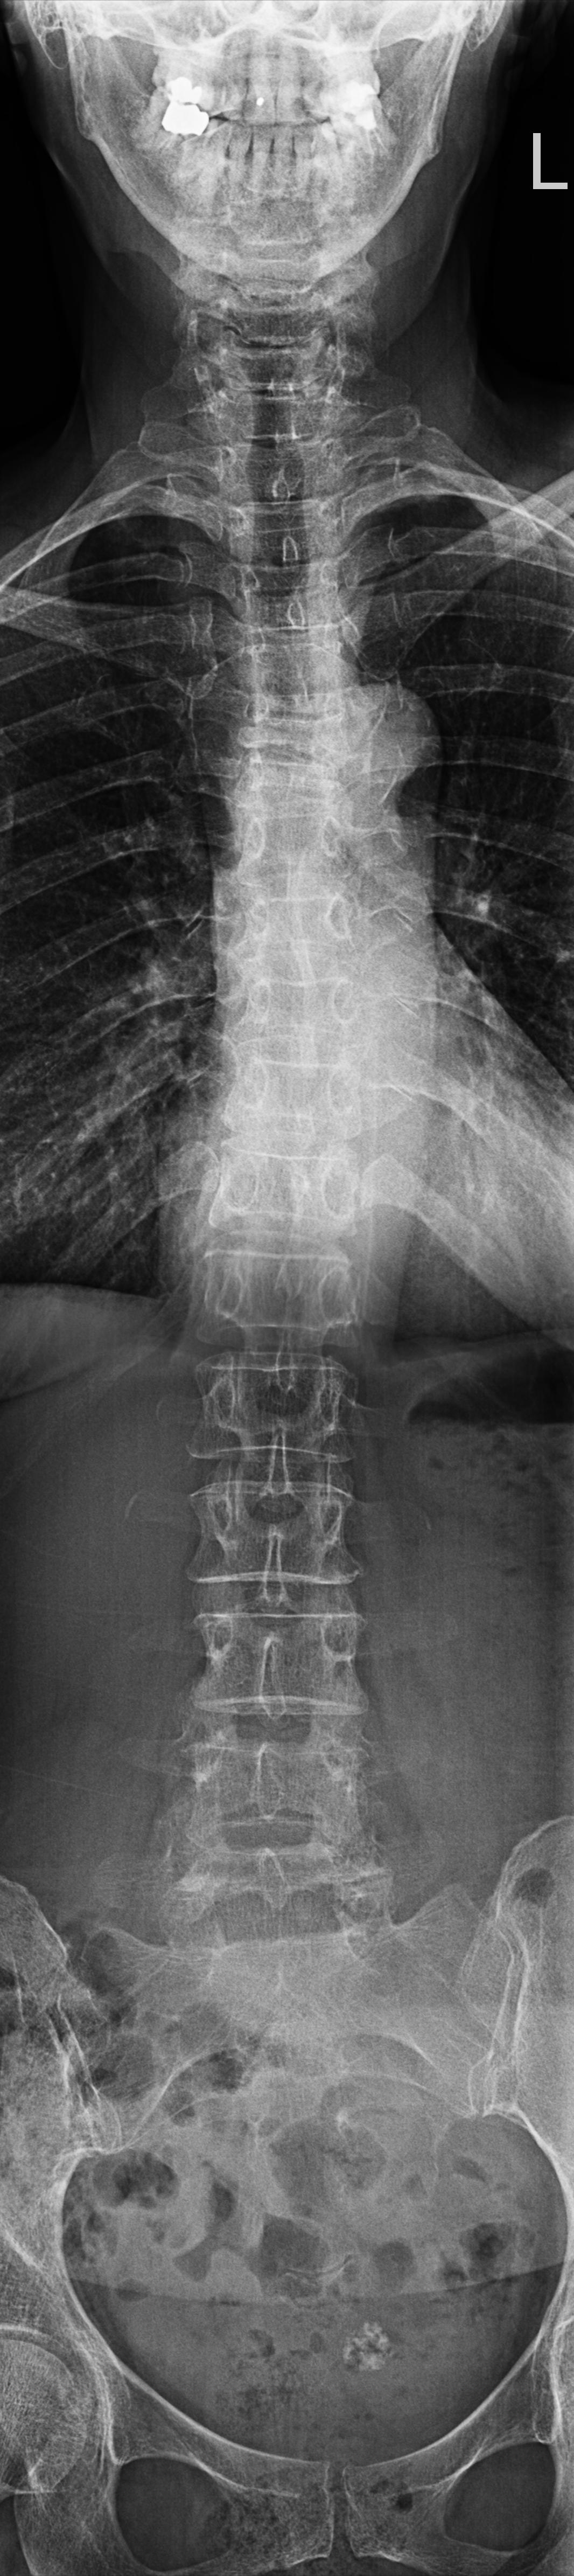

Wirbelsäule Ganzaufnahme a.-p.

Es wurden keine Bilder gefunden.

Technik

• FDA: 3 m

• Ausgangsformat: 3 x 35/43

• mit Raster

Indikation

Beurteilung der Wirbelsäule und des Beckens bei Schiefstand.

Lagerung

Mit dem Rücken am Rasterwandstativ

Kopf leicht nach hinten nehmen

Arme an der Seite

Zentralstrahl

Senkrecht auf Wirbelsäule

Einblendung

von Oberlippe bis einschließlich Hüftköpfe.

Qualitätskriterien

HWS-BWS-LWS mit Sakrum sollte vollständig und gut beurteilbar abgebildet sein.

Anmerkung

Spezialstativ mit Raster oder Digitalaufnahme mit Abbildung eines Rasters zur Vermessung. Evtl Ausgleichschuhe ausziehen und auch ggf. Verlaufsfilter für guten Kontrast verwenden.